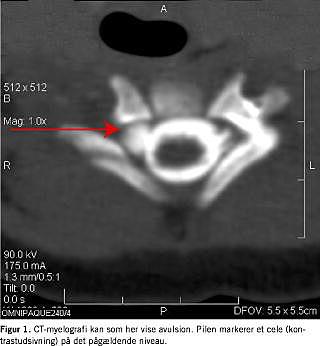

Der findes i det store og hele to patientkategorier: 1) Store nyfødte med høj fødselsvægt (ofte over 4 kg) i hovedstilling og med skulderdystoci. Det kræver stor trækkraft (ikke sjældent med anvendelse af tang eller kop) at forløse barnet. Dette resulterer i skade på øverste del af plexus brachialis, som regel C5 og C6, af og til også C7. Aldrig de nedre nerverødder (C8 og T1) (Figur 1 ), 2) underkropspræsentation af små (ofte under 3 kg) nyfødte, som kræver kraftig ekstention af hovedet og ikke sjældent manipulation af hånd og arm, medførende træk på både øvre og nedre nerverødder. Dette kan forårsage avulsion af en hvilken som helst eller i sjældne tilfælde alle nerverødder til plexus brachialis (Figur 2 ).

Det kliniske billede vil udvikle sig meget varieret i løbet af de første måneder, og mange pareser vil forsvinde i dette stadie [7]. Der vil dog være mange patienter, som ikke restitueres fuldt, således fandt Wickstrom et al, at kun 10% af børnene med komplette læsioner opnåede en brugbar funktion af armen [8]. Disse patienter skal reevalueres klinisk 3 mdr. gamle, og der suppleres eventuelt med elektromyografi og CT-myelografi (Figur 1). Der bør altid straks indledes fysioterapi for at modvirke kontrakturer (specielt indadrotationskontrakturer i skulderen) af fungerende muskler og ledkapsel, mens man afventer spontan bedring. På dette stadie vil en komplet parese med tilstedeværende Horners syndrom forblive uændret, og der bør planlægges tidlig operation i tremånedersalderen.

Myelografi er meget anvendt. Ordinær myelografi (under anvendelse af konventionel røntgen-teknik) giver mange falsk negative og falsk positive resultater. I dag er mængden af disse minimeret ved den mere sofistikerede CT-myelografi.